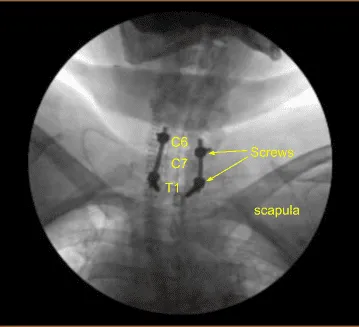

Image-guided stereotactic frame with neuronavigation techniques were used to place the instrumentation. We placed bilateral T1 pedicle screws and decorticated with electric high-speed drill cannulating with the navigated pedicle finder, palpating for breaches, measuring the depths, under tapping by 11 mm and placing 30 mm x 5.0 mm titanium pedicle screws bilaterally without difficulty.

Next, we placed bilateral lateral mass screws at C6. Inspecting the deformity of the spine, a decision was made not to place the C5 lateral mass screws because of kyphotic deformity and difficulty with rod placement.

So, we next decorticated the joints at C6-C7 and C7-T1 and bilateral T1 transverse processes with electric high-speed drill for the arthrodesis. The autograft resected was morselized. Precut-precontoured titanium rods were placed across the tulips from C6 to T1 and secured with locking caps and then final tightened with a torque and anti-torque device.